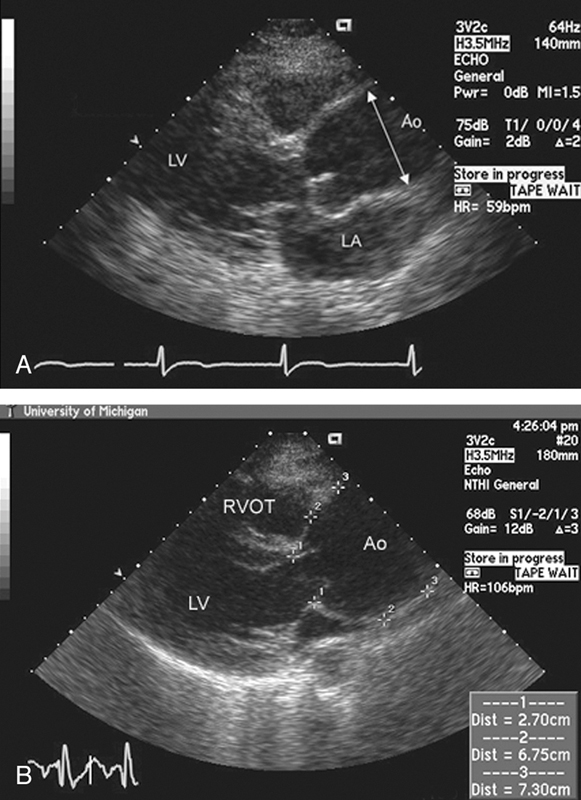

فحوصات تشخيصية لبعض امراض القلب والشرايين التاجية